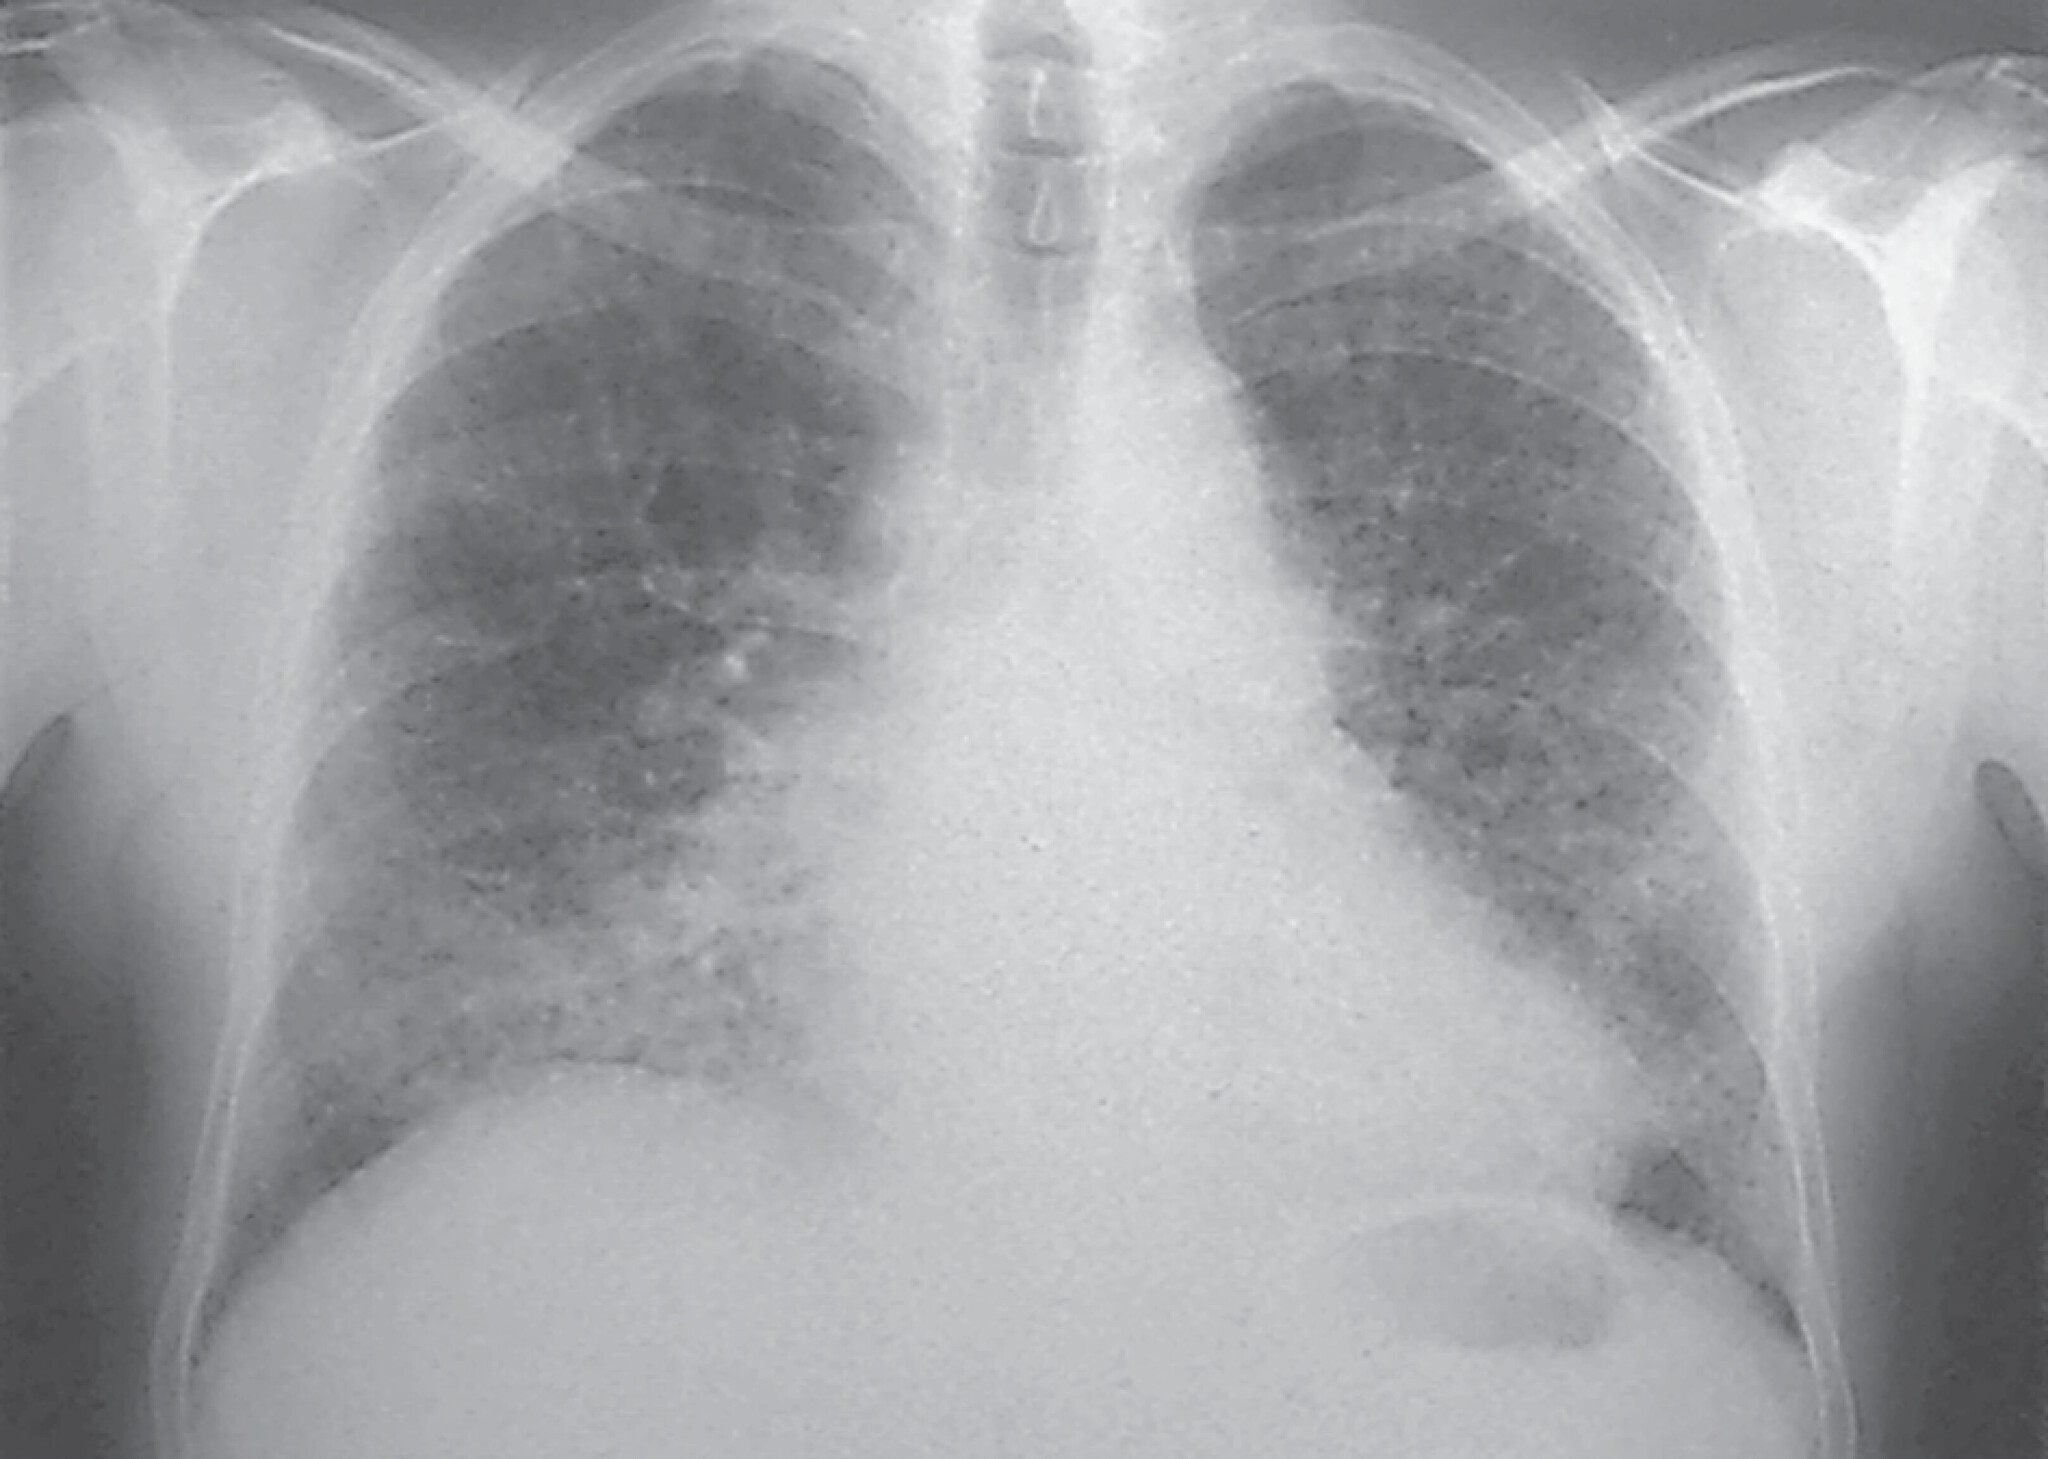

Besteht der Verdacht einer Sarkoidose, sollte eine Röntgen-Thorax-Übersicht durchgeführt werden. Die Lungensarkoidose kann nach dem Röntgen-Thorax-Befund in vier Röntgentypen eingeteilt werden (Abb. 27.8):

- Typ I: beidseitige Hilusadenopathie ohne pulmonale Beteiligungen

- Typ II: beidseitige Hilusadenopathie mit pulmonalen Beteiligungen

- Typ III: pulmonale Beteiligungen ohne Hilusadenopathie

- Typ IV: Zeichen der Lungenfibrose.

Bei Erkrankungen vom Typ I können bei 70–90% der Fälle innerhalb eines Jahres spontane Remissionen erwartet werden, vor allem, wenn ein Löfgren-Syndrom vorliegt (akute Sarkoidose). Beim Typ II findet man immerhin noch 50% Spontanremissionen.

Abb. 27.8 Sarkoidose

b Chronische Sarkoidose Röntgentyp II. 47-jährige Frau. Disseminierte kleinfleckig-streifige, z. T. konfluierende Konsolidierungen beider Lungen, geringe Hiluslymphome beidseits. Die Patientin ist symptomfrei.